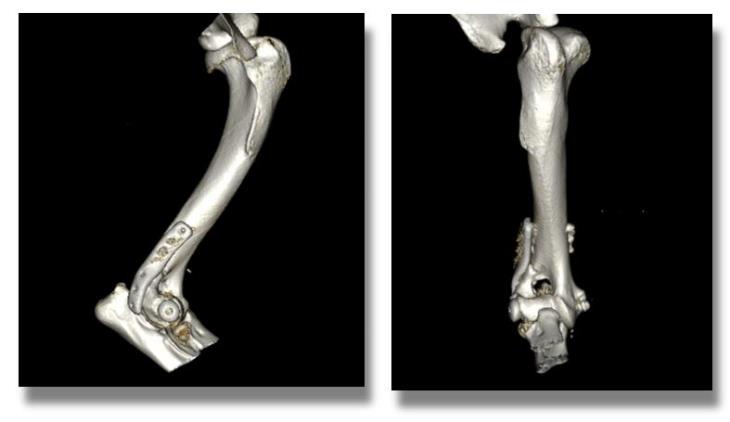

This patient underwent surgery and made a good recovery from his general anaesthetic.

His postoperative CT scans below show excellent apposition and alignment of the bone fragments and restoration of a normal joint surface.